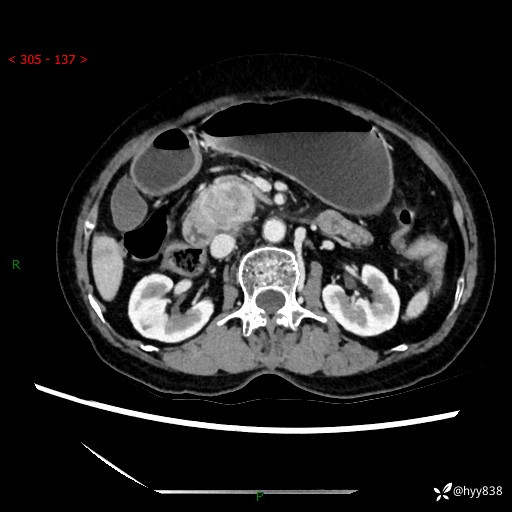

71岁/女,腹痛1月余。腹膜后肿物,间质瘤 VS 副节瘤 VS 平滑肌肉瘤---(有结果)

【患者信息】:71岁/女

【主诉】:腹痛1月余

【现病史及既往史】:患者于1月前无明显诱因出现右下腹部疼痛不适,呈阵发性隐痛,尚可耐受,放射至后背部及腰部疼痛,伴排便困难,不伴其它部位疼痛,无嗳气,无不洁饮食,无黑便,无恶心、呕吐、腹胀腹泻、呕血、发热、寒颤、厌油、黄疸,多次就诊于当地区太湖医院拍片示: 行抗炎等对症支持治疗,效果尚可。现患者上述不适症状明显进一步加重,为求进一步治疗遂来我院门诊就诊,门诊以“十二指肠肿瘤?”收住我科。 起病以来,精神、睡眠可,食欲可,大便异常、小便正常,体力、体重无明显下降。

【检查】:腹部CT增强扫描(外院CT平扫)